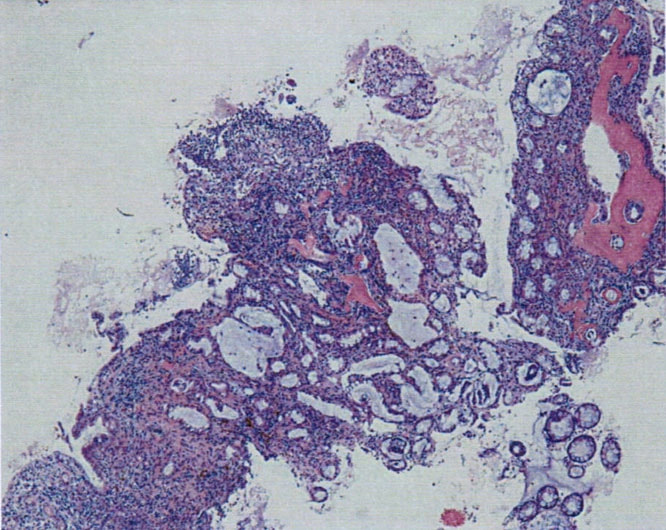

症例:炎症性ポリープ M.ダックス 10歳 オス

主訴:8ヶ月前から便が細くなり、血が混じることがある。その他、元気・食欲等、一般状態は良好。

経過:超音波検査にて直腸壁の肥厚(5㎜)が認められた。また、直腸検査で直腸全周に結節状病変を触知し、出血も確認された。消炎剤、抗生剤、整腸剤による治療への反応が長期的に悪いため、生検も含めた内視鏡検査を実施した。

内視鏡検査:肛門付近の直腸全周に、炎症および出血を伴う結節状病変を多数認めた。

病理検査:直腸の病変は、良性の非腫瘍性病変の一つである“炎症性ポリープ”と診断された。

診断後経過:炎症性ポリープは多発する傾向や腫瘍に転化する可能性があるため、消炎剤、抗生剤、整腸剤による内科療法を継続しながら、現在プルスルー法による外科的摘出術を検討中。

◎炎症性ポリープとは

近年、ミニチュアダックスで好発が知られている良性の腫瘍性の病変です。しばしば多発し、また腫瘍に転化する事があります。